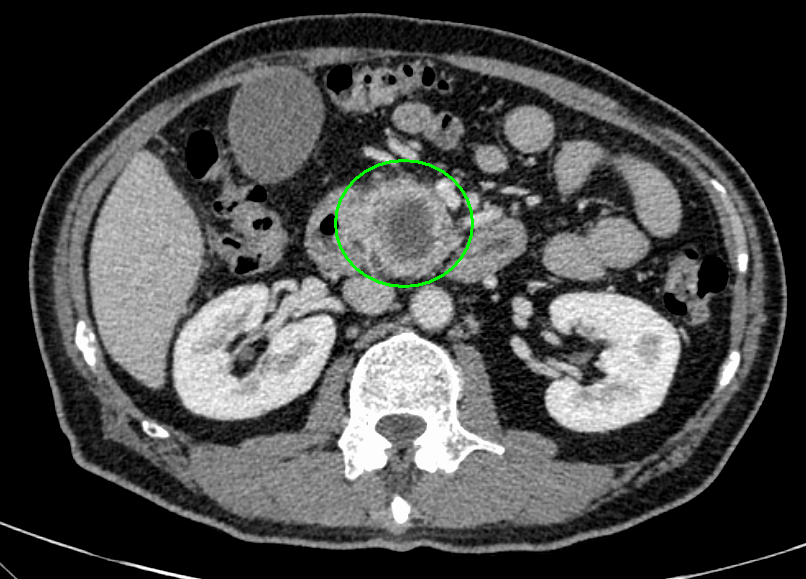

- 造影CT

術前シミュレーション画像(CT画像)

術前化学療法の治療例

治療前

治療後